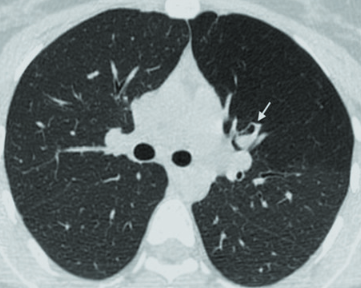

Облитерация легкого

Облитерация легкого 104 фото